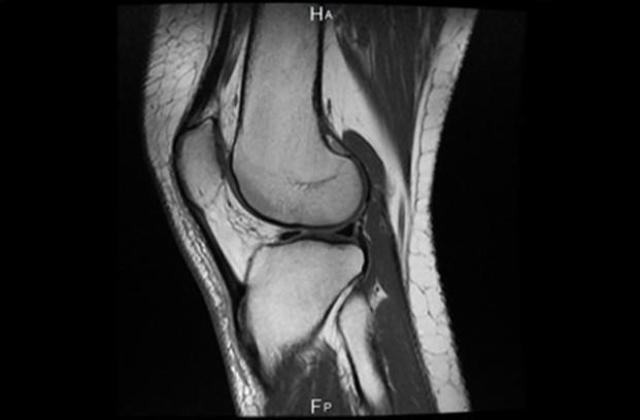

МРТ суставов

МРТ суставов — один из самых передовых и информативных методов исследования в современной медицине. Данный вид диагностики позволяет обнаружить аномалии развития и патологии тканевых структур в суставах, тщательно изучить близлежащие кровеносные сосуды и нервные окончания.

МРТ-исследование позволяет спроецировать внутреннее строение суставов на экран аппарата, на нем лучше, чем на рентгене и УЗИ, видны кости, хрящи, сухожилия, мениски, мышечная ткань, связки.

МРТ суставов относится к высокоточным способам диагностики, томограф производит обследование в трехмерной проекции, на снимках хорошо визуализируются даже незначительные изменения, поэтому многие болезни могут быть обнаружены в начале их развития, и правильно поставленный диагноз в данном случае позволяет вовремя начать лечение заболевания и предотвратить возможные осложнения.

Применяется магнитно-резонансная томография при исследовании крупных суставов: плечевых, локтевых, тазобедренных, коленных, голеностопных.